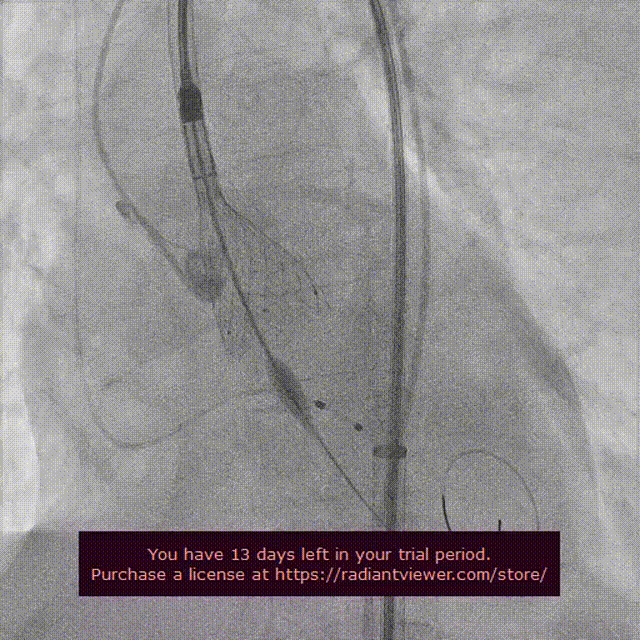

瓣膜第一次释放造影

起搏150次/分,VenusA-Plus®L26标准位快速释放,释放至三分之二处,造影发现瓣膜位置不佳,下滑严重,快速进行回收,重新定位释放,造影发现第二次释放位置良好。

瓣膜位置下滑进行回收